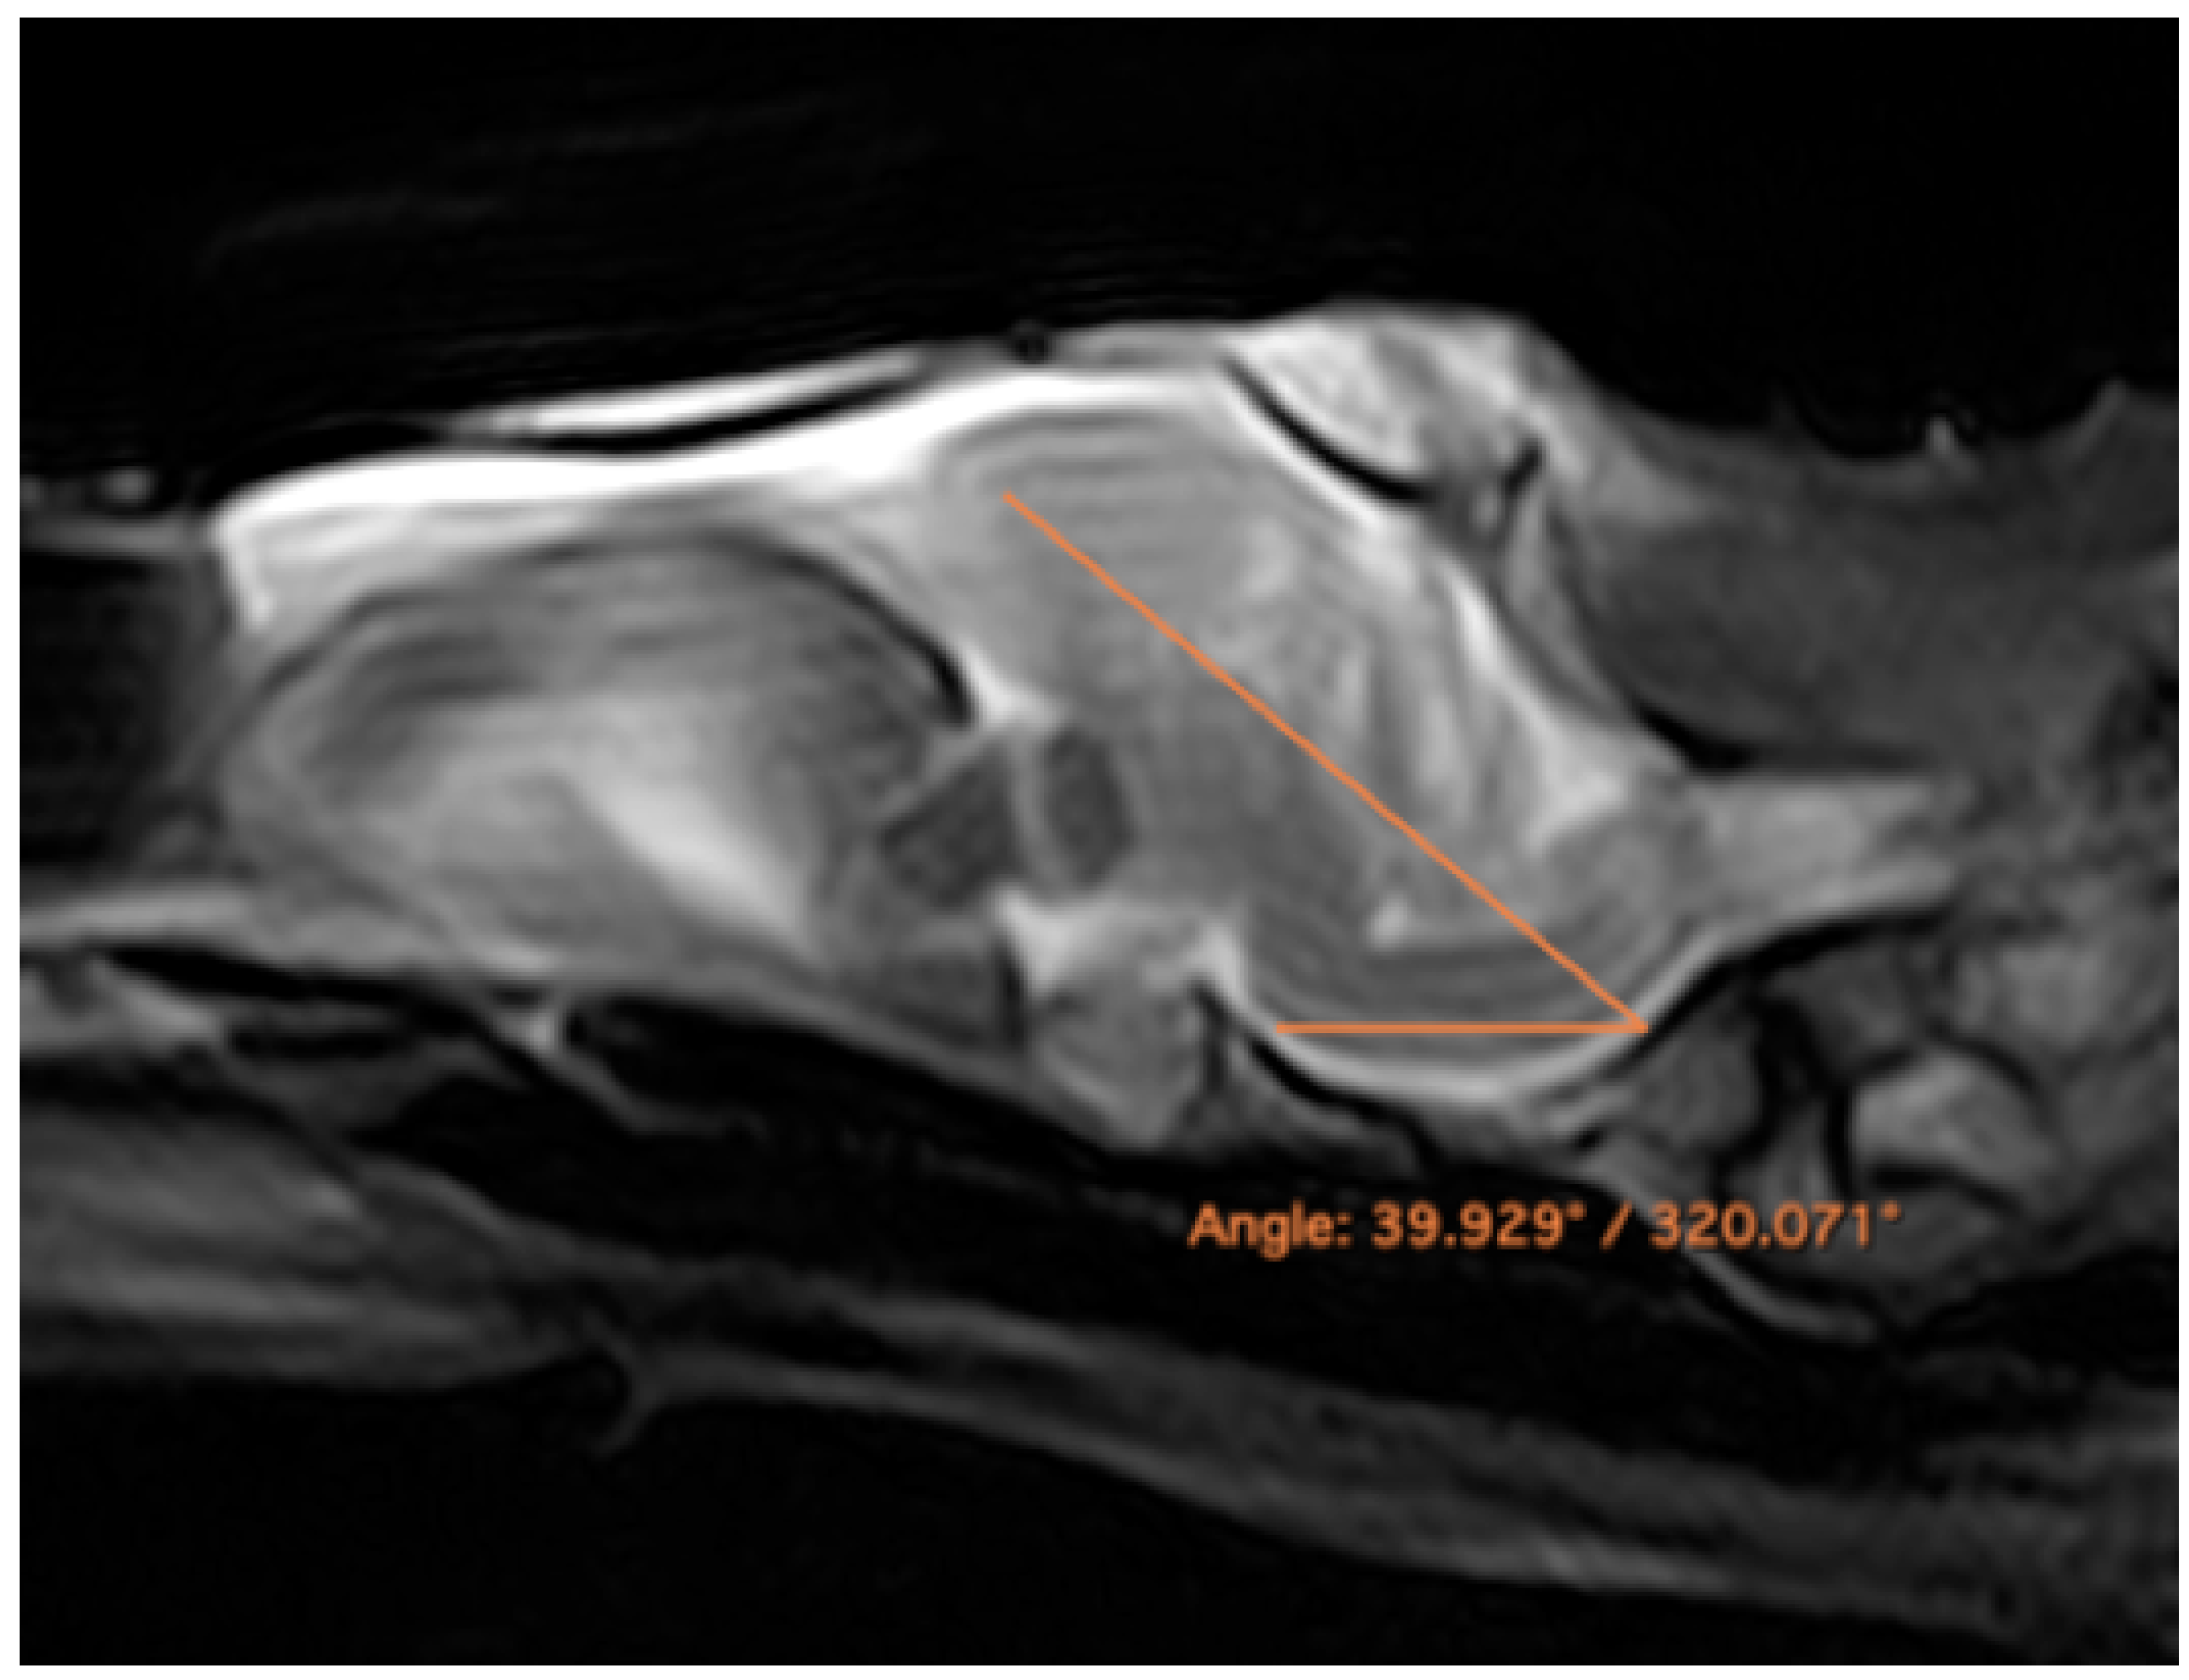

Figure 1 corresponds to a bone-window CT sagittal plane, in which each line and number (I–V) represents approximately the level of the following anatomical, CT and MRI transverse planes. Transversal sections revealing the relevant anatomical structures of the rhinoceros iguana head are presented (Figure 2, Figure 3, Figure 4, Figure 5 and Figure 6). Figure 2, Figure 3, Figure 4, Figure 5 and Figure 6 are composed of three images: (A) macroscopic, (B) bone window CT and (C) MRI. The images are presented in a rostrocaudal progression from the maxillary bone (Figure 2) to the brainstem levels (Figure 6). Figure 7 and Figure 8 are composed of two images: (A) bone-window CT and (B) MRI in T2W, in a dorsal and sagittal plane, respectively. Figure 9 is a T2W sequence sagittal image showing the angulation concerning the horizontal axis of the myelencephalon (40°).

Figure 9.

Rhinoceros iguana encephalic angulation, sagittal T2W image with respect to the horizontal axis of the myelencephalon (40°).

In addition, the MRI and CT findings showed a greater angulation concerning the horizontal axis of the encephalon, with an angulation of 40° between the central horizontal axis of the skull and the central axis of the encephalon (dorsal displacement concerning the encephalon of the dog) (Figure 9), differing from other studies where an angulation of 28° was described [31]. In galliform birds, the brain has a similar angulation to the skull axis [32]. More similar aspects to the latter were found, such as the large size of the eyeballs, which were almost as large as the whole encephalon [32]. Nonetheless, further studies with a large number of animals should be performed to confirm these findings.